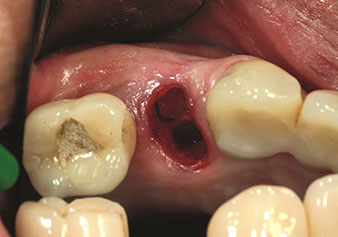

Alveolar management

One application, which is often underestimated is the atraumatic extraction of tooth roots or root fragments in the scope of alveolar management. The fine periotomes, which are currently available in two versions (EX1 and EX2 from W&H), can also be used to remove teeth which have previously undergone special endodontic treatment or ankylosed roots with ease. This results in extraction alveoli where both the hard and soft tissue are fully intact as it is generally possible to avoid reflection.

This establishes the optimal basis for subsequent or immediate implant treatment (Figures 1 and 2 included with the kind permission of Dr Torsten Conrad, Bingen a. Rhein).

Situation following piezosurgical extraction

Fig. 2: Situation following piezosurgical extraction. Photo: © Dr Torsten Conrad (Bingen am Rhein)